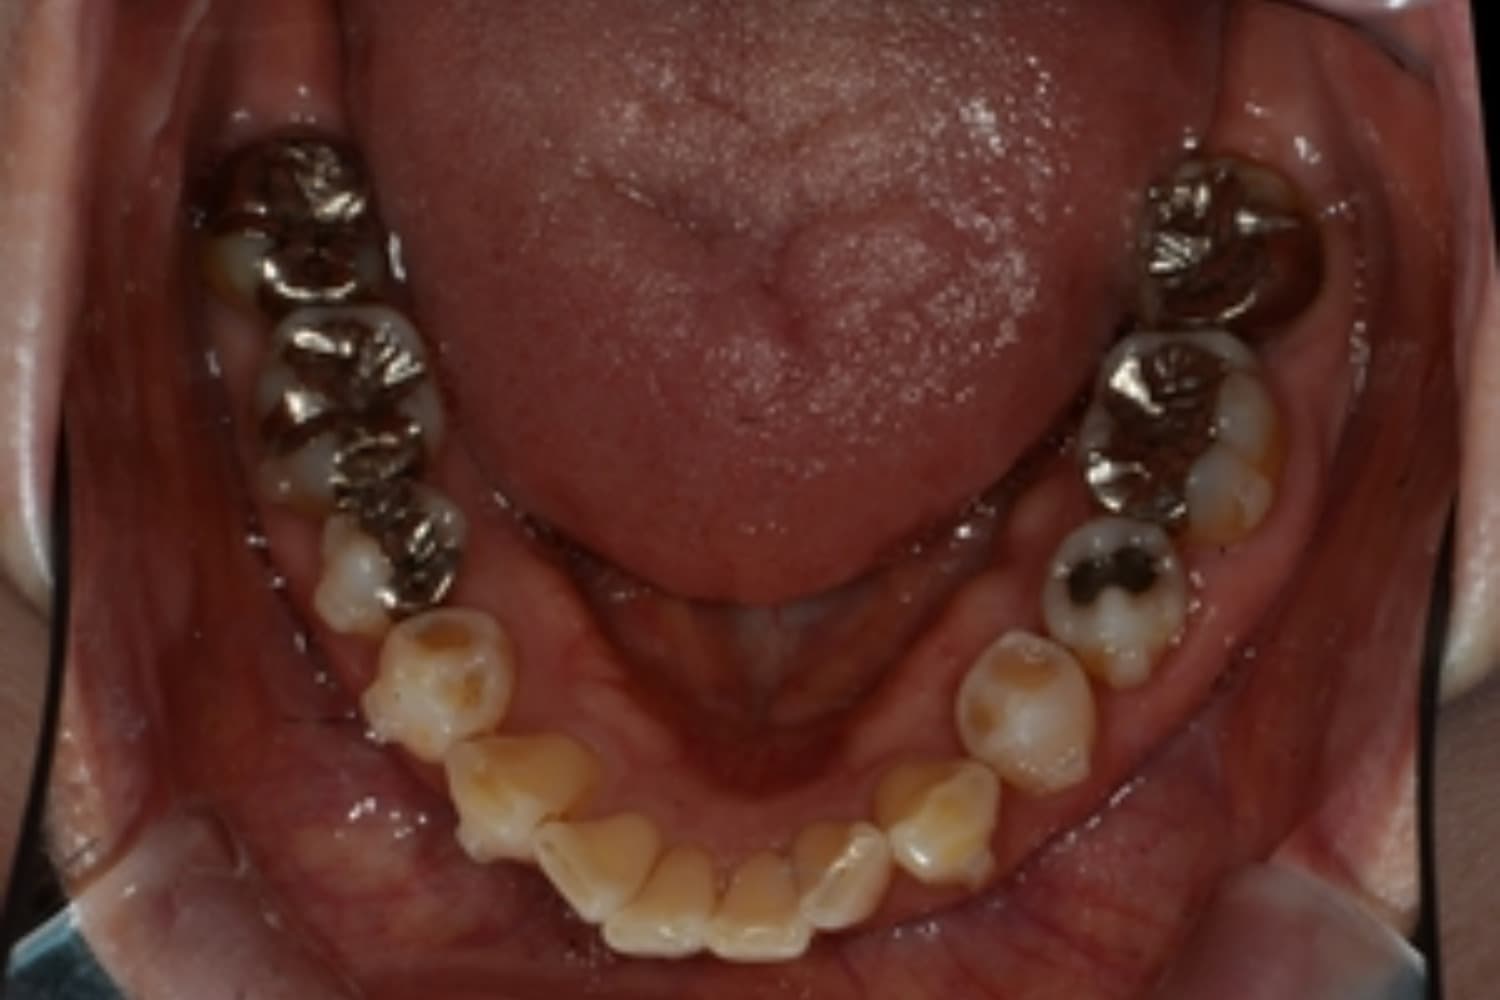

下顎大臼歯3本欠損症例

Before

After

左下第一大臼歯は保存が困難な状態であったため抜歯をおこないました。あわせて、ご来院時から欠損していた右下第一・第二大臼歯も含め、欠損部の補綴方法についてご説明し、インプラント治療を選択されました。

年齢

60歳

性別

男性

主訴

左下の第一大臼歯は別の医院で治療中でしたが、治療が思うように進まず、加えて他の箇所にも痛みが続いたことから、当院にご相談いただきました。

治療期間

10ヵ月

費用

140万円

副作用・リスク

インプラント治療は外科的な処置を伴い、多少の腫れや痛みが出ることがあります。 多くの場合は鎮痛薬で和らげることができます。